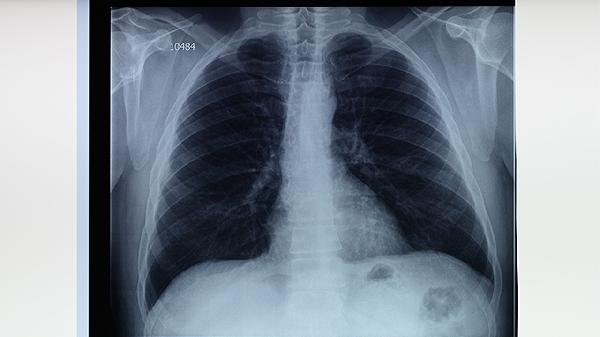

肺結(jié)核的發(fā)病因素主要有結(jié)核分枝桿菌感染、免疫力低下、密切接觸傳染源、居住環(huán)境擁擠以及合并慢性疾病等。

結(jié)核分枝桿菌是引起肺結(jié)核的主要病原體,通過(guò)空氣飛沫傳播。當(dāng)感染者咳嗽、打噴嚏或說(shuō)話(huà)時(shí),會(huì)將含有結(jié)核分枝桿菌的飛沫釋放到空氣中,他人吸入后可能被感染。感染后是否發(fā)病與個(gè)體免疫力有關(guān),免疫力較強(qiáng)的人可能不會(huì)出現(xiàn)癥狀,但免疫力低下時(shí)容易發(fā)展為活動(dòng)性肺結(jié)核。